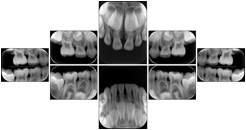

2. A patient requests cosmetic surgery to enhance their facial appearance. The case requires consultation between an orthodontist in New York and an oral surgeon in California. The cephalometric series of 2D projections constructed from a volumetric CT data set that is used for the discussion is arranged by a Structured Display for transfer between the two practitioners.

Cephalometric Series Structured Display

Figure OO-2. Cephalometric Series Structured Display